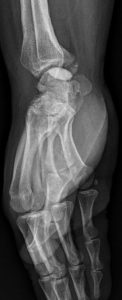

L’imagerie joue un rôle essentiel dans le diagnostic de la maladie de Kienböck et permet de déterminer son stade. La radiographie standard reste le premier bilan à réaliser. Elle permet de voir les fractures ou la déformation du lunatum dans les formes avancées de la pathologie. Cependant, les premiers stades de la nécrose peuvent ne pas être visibles sur les radiographies classiques.

Traitement chirurgical : Décompression osseuse

La décompression osseuse est l’une des techniques de référence dans les formes précoces de la maladie de Kienböck (stades I et II de Lichtman). Elle vise à améliorer la vascularisation du lunatum en réduisant les contraintes mécaniques qui s’exercent sur lui, notamment lorsqu’il est « coincé » entre le radius et le capitatum.

Plusieurs ostéotomies peuvent être réalisées selon la morphologie du poignet et la cause mécanique suspectée :

- Ostéotomie de raccourcissement du radius : on retire une fine lamelle osseuse du radius distal afin de diminuer la pression exercée sur le lunatum et de redistribuer les contraintes.

- Ostéotomie de raccourcissement du capitatum : cette variante plus rare consiste à raccourcir légèrement le capitatum pour limiter son impact compressif sur le lunatum.

Dans les suites, une immobilisation du poignet est nécessaire jusqu’à consolidation du trait d’ostéotomie, généralement pendant plusieurs semaines.

Cette approche chirurgicale donne de bons résultats aux stades précoces, avec une diminution notable des douleurs et parfois une stabilisation de l’évolution de la maladie. Elle est particulièrement indiquée chez les patients jeunes, actifs, et dont le lunatum est encore viable, car elle permet de préserver l’articulation et de retarder (voire éviter) le recours à des gestes plus lourds.